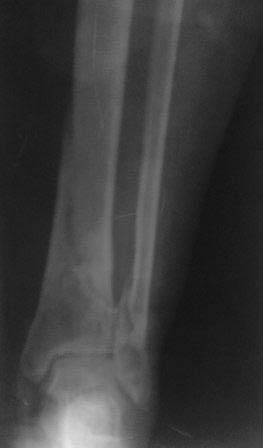

Re: Вялоконсолидирующийся перелом дистального метадиафиза костей левой голени

Р-снимки после закрытой остеоклазии и коррекции деформации, а также после фиксации аппаратом, дистальные спицы прошли близко к линии излома но фиксация стабильная, деформация клинически исчезла,

больная довольна, начала ходит дозированной нагрузкой.

С уважением Абдурашид.